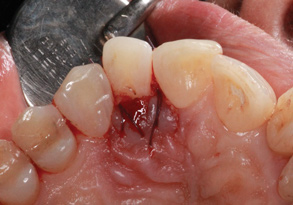

(3.) Surgical photograph of tooth No. 7 exhibiting grooves extending to root, severe bone loss, lack of palatal plate, and excess enamel malformation.

Figure 3

The patient was premedicated with an antibiotic (ie, clindamycin 150 mg; orally, three times daily) and an analgesic (ie, Motrin 800 mg; three times daily, as needed). To enable access to the root and bony defects, two vertical incisions were made on the midpalatal aspects of teeth Nos. 6 and 8 and horizontal incisions were made from tooth No. 6 to tooth No. 8 using a No. 12 scalpel blade (Carbon Steel, Benco Dental). This flap reflection enabled the visualization of significant bone loss and missing palatal plates on tooth No. 7. The magnitude of the gingival groove (ie, length and depth) was also evaluated prior to elimination. Using a fine diamond bur, the large fold of enamel extending to the coronal third of the root was reduced and the deep grooves were eliminated. After the bony defect on the midpalatal and mesial aspect of tooth No. 7 was grafted with particulate freeze-dried bone allograft (Cortical bone, Maxxeus Dental) and covered with a resorbable membrane (Bio-Gide®, Geistlich Pharma North America, Inc.), the flap was closed with PGA sutures (Figure 3 through Figure 5).